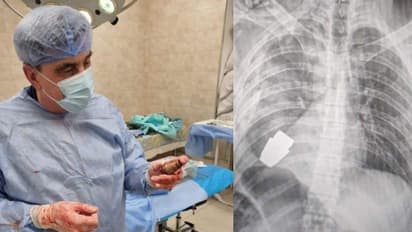

ഓപ്പറേഷന് വിജയകരമായതിനെ തുടര്ന്ന് സൈനികന് ഇപ്പോള് വിശ്രമത്തിലാണ്. ശസ്ത്രക്രിയയ്ക്ക് ശേഷം ഡോക്ടറെ അഭിനന്ദിച്ചുകൊണ്ട് യുക്രൈന് സായുധസേന പോസ്റ്റ് ചെയ്ത ഫേസ്ബുക്ക് കുറിപ്പിലൂടെയാണ് ഈ വിവരം പുറത്തുവന്നത്. ശസ്ത്രക്രിയയ്ക്ക് മുമ്പുള്ള സൈനികന്റെ എക്സ്റേ ചിത്രവും ശസ്ത്രക്രിയയ്ക്ക് ശേഷം പുറത്തെടുത്ത ഗ്രനൈഡുമായി നില്ക്കുന്ന ഡോക്ടറിന്റെ ചിത്രവും ഫേസ്ബുക്ക് കുറിപ്പിനോടൊപ്പം ചേര്ത്തിട്ടുണ്ട്. ഫേസ്ബുക്ക് പോസ്റ്റ് വൈറല് ആയതോടെ നിരവധി ആളുകളാണ് ഡോക്ടറുടെ ധീരതയെ അഭിനന്ദിച്ച് കമന്റുകളുമായി രംഗത്തെത്തിയത്.